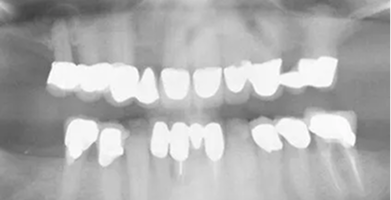

Single Implants

Ideal for replacing one missing tooth without affecting surrounding teeth.

BEFORE

AFTER